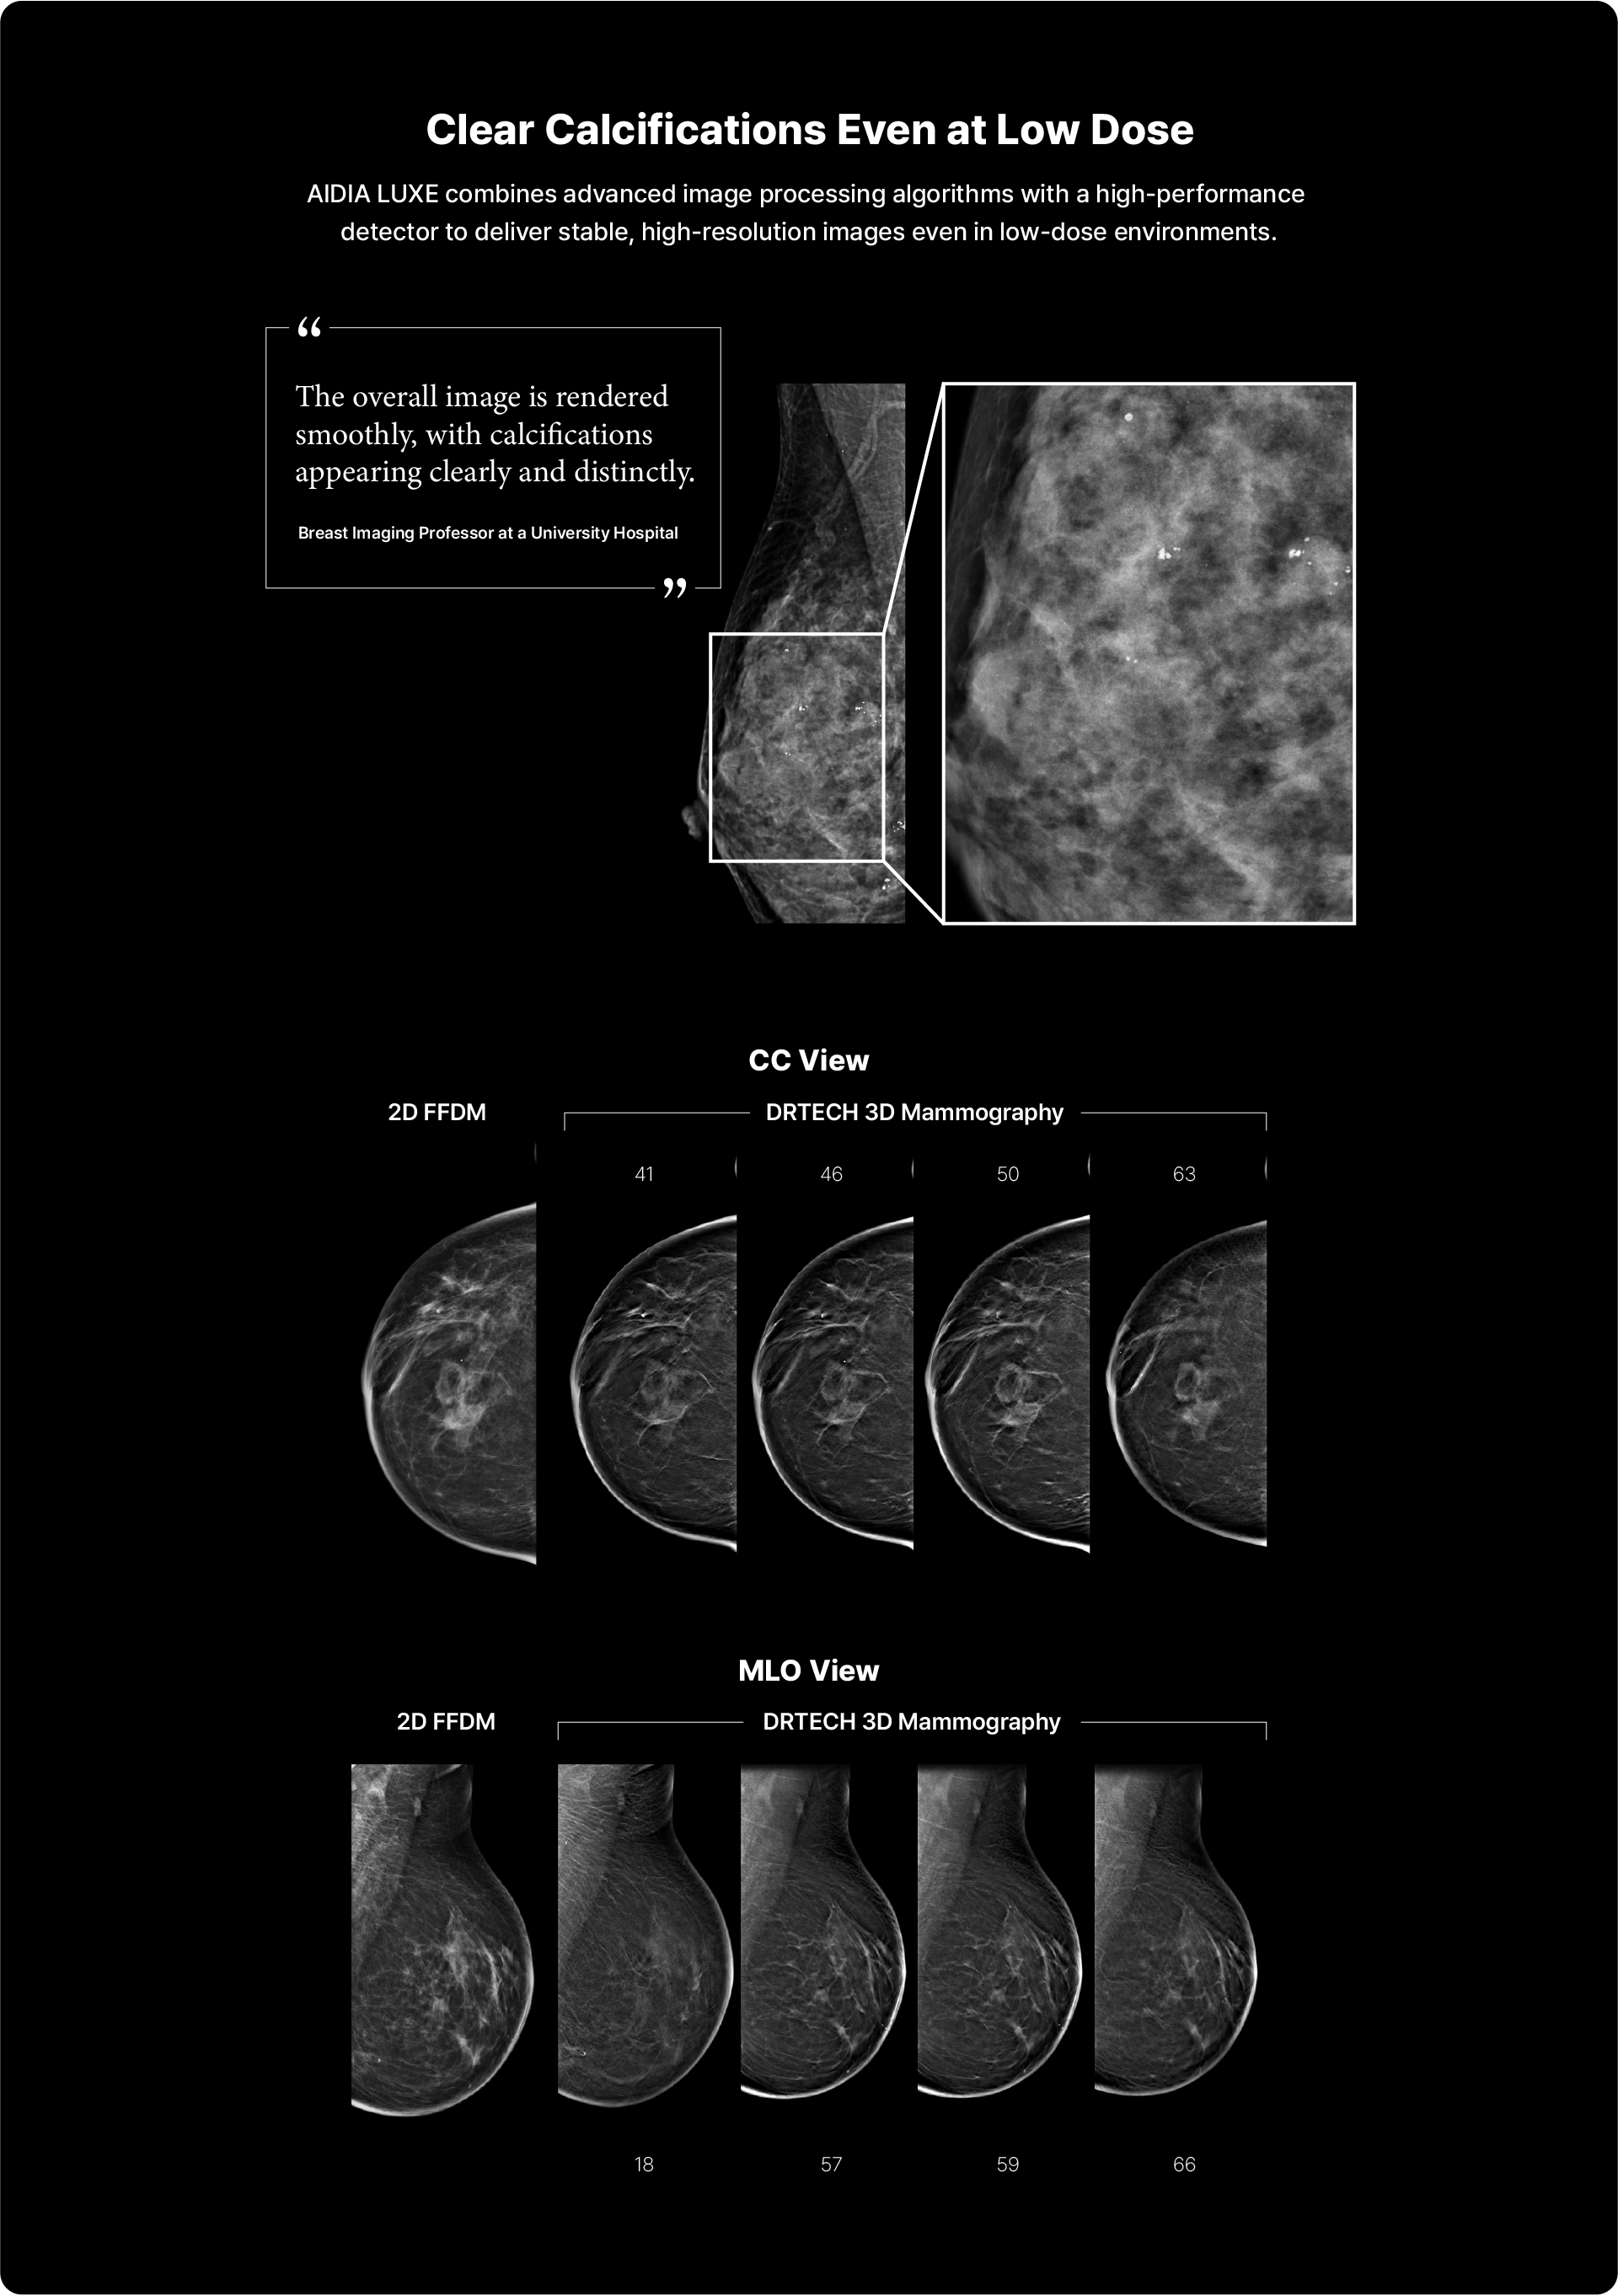

- Clear sharp images with well-depicted visualization of micro-calcifications

TRUVIEWยฎM2:AI Image Processing Technology for Accurate Breast Imaging

With AIDIA's proprietary AI post-processing technology optimized:

- for various breast densities and tissue types, even the finest details

can be accurately identified.